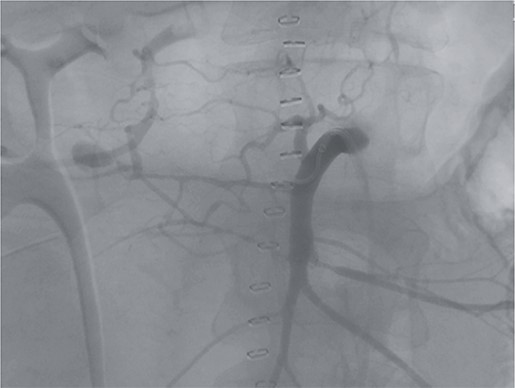

Postoperatively, the patient achieved hemodynamic stabilization in the intensive care unit. On the sixth postoperative day, there was a recurrence of circulatory collapse in addition to relevant bloody discharge through the drains. CT imaging once again revealed an active bleeding of the pancreaticoduodenal artery, which was successfully treated interventionally using coiling (Figs 2 and 3).

Angiography revealing the aneurysm of the pancreaticoduodenal arcade.